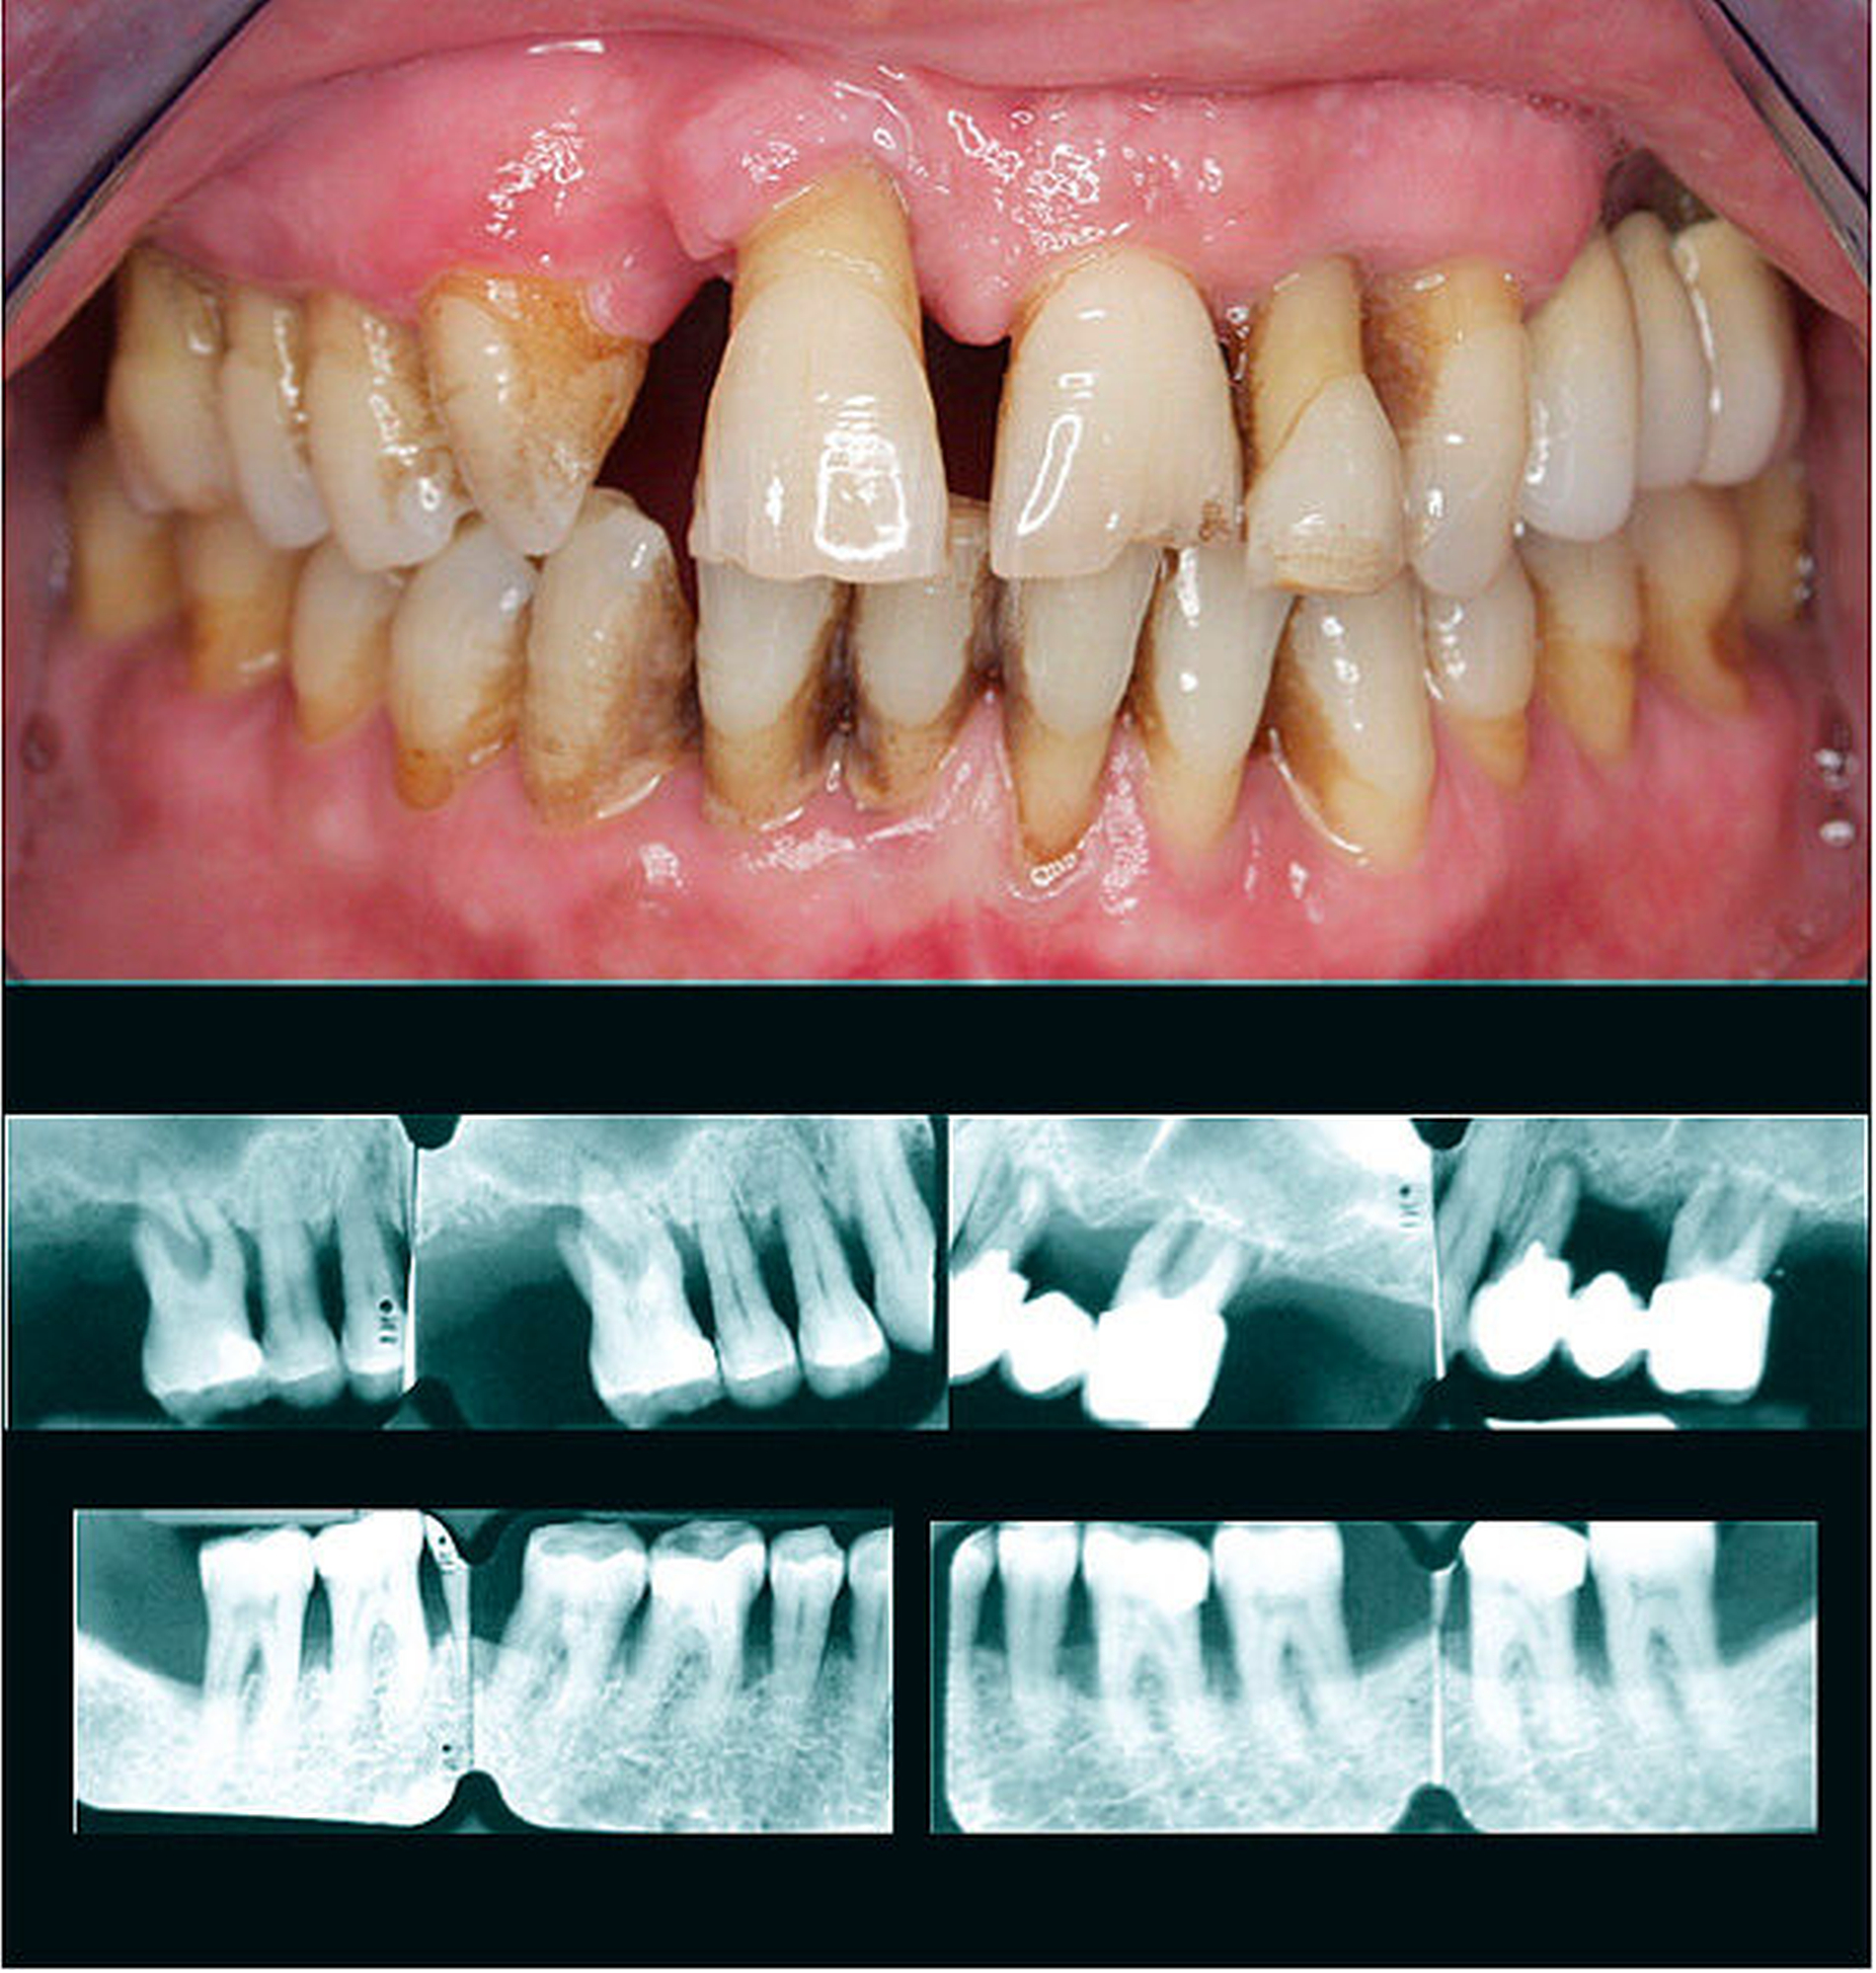

Die Diagnose ist Stadium IV, wenn:

(a) BL in das mittlere Drittel der Wurzel oder darüber hinaus reicht,

(b) CAL 5 mm oder mehr beträgt,

(c) PTL mehr als vier Zähne ist,

(d) es weniger als zehn okkludierende Zahnpaare gibt oder

(e) wenn es einen Bisskollaps, Zahnwanderung, Auffächerung oder einen schweren Kammdefekt gibt.

Der Schwere-Wert basiert hauptsächlich auf dem interdentalen Attachmentverlust, der auf Parodontitis zurückzuführen ist, und dem marginalen Knochenabbau. Er wird bezogen auf den am stärksten betroffenen Zahn zugeordnet. Der Komplexitäts-Wert basiert auf der Komplexität der Behandlung des Falles. Er berücksichtigt Faktoren wie das Vorhandensein von ausgedehnten Sondierungstiefen, vertikalen Defekten, Furkationsbeteiligung, Zahnhypermobilität, Wanderungen und/oder Auffächerungen von Zähnen, Zahnverlust, Alveolarkammdefekten und Verlust der Kaufunktion.

Um das Stadium eines individuellen Parodontitis-Falles festzustellen, sind folgende Informationen erforderlich: vollständiger Röntgenstatus, ein Parodontalstatus und die parodontale Vorgeschichte des Zahnverlusts (periodontal history of tooth loss, PTL). Zuerst bewerten wir das Ausmaß der Erkrankung, indem beurteilt wird, ob CAL/BL weniger als 30 Prozent der Zähne (lokalisiert) oder 30 Prozent und mehr betrifft (generalisiert). Dann definieren wir das Stadium der Erkrankung, indem wir die Schwere (mit CAL, BL und PTL) und Komplexität (durch die Beurteilung von PPD, Furkations- und intraossären Läsionen, Zahnhypermobilität, sekundärem okklusalem Trauma, Bisskollaps, Zahnwanderung, Auffächern oder weniger als zehn okkludierende Zahnpaare) bestimmen.